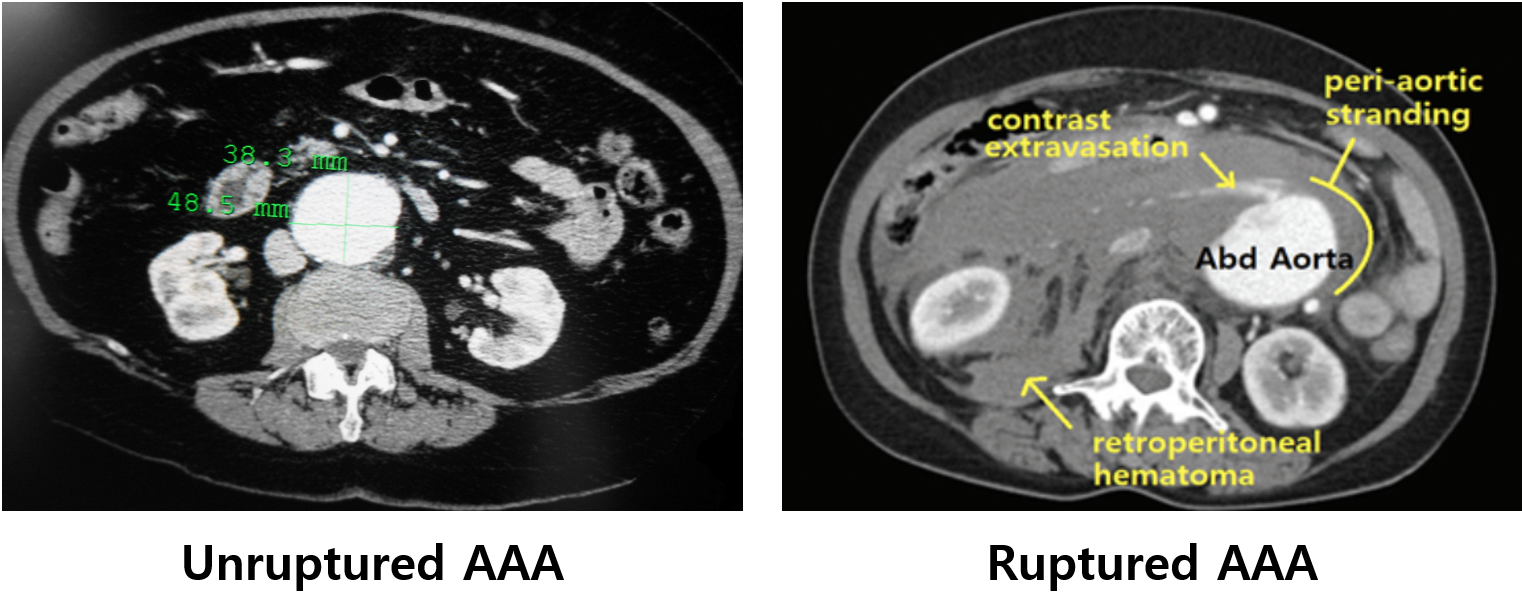

2) CT(조영증강): 다음을 파악해 치료방침을 결정할 때 유용

(1) 병변의 위치와 크기

(2) 석회화, 혈전 등

(3) 대동맥 파열 여부